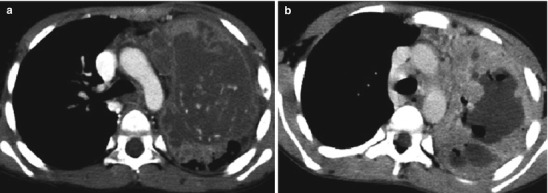

Lymphadenopathy (present in 92 %) with or without a visible Ghon focus is the radiographic hallmark of TB infection and usually involves the hilar and paratracheal regions. The Ghon focus may be too small to be radiographically visible but can also undergo caseation and calcify (Fig. 13.17). Disease progression may occur at the site of Ghon focus, within the regional lymph nodes, or following disease spread (Fig. 13.18). Parenchymal involvement in primary pulmonary TB most commonly appears as homogeneous consolidation, although it can appear patchy, linear, nodular, and mass-like. Caseation necrosis, liquefaction, or calcifications can be seen within the consolidation and can progress into extensive lung damage (Marais et al. 2004) (Fig. 13.19). Enlarged and edematous hilar, paratracheal, and subcarinal lymph nodes may cause compression of the adjacent bronchus and can lead to hyperinflation or atelectasis of the affected lung segment. Contrast-enhanced CT shows a characteristic appearance consisting of central areas of low attenuation with peripheral rim enhancement and obliteration of perinodal fat (Kim et al. 1997) (Fig. 13.20).

Fig. 13.19.

Progression of Ghon focus. CT scan images from two different patients showing advanced progression of lung parenchymal disease from dense consolidation with ischemic changes (a) and cavitary necrosis with cyst formation (b)